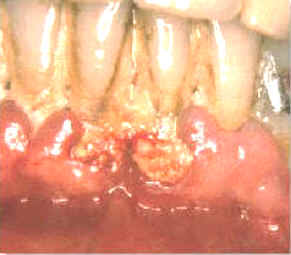

| Estas imágenes muestran inmediatamente como queda luego

de la limpieza con instrumental ultrasónico.

La gingiva se desprende del diente y la mayoría del epitelio de la

bolsa periodontal queda expuesto. El sangrado durante el tratamiento es intenso y el paciente

suele notar algún sangrado post operatorio de la encía. Los tejidos

blandos suelen molestar. |

| Durante algunos días el paciente al comer y

cepillar sus dientes, puede presentar síntomas de dolor y sangrado.

Suele ocurrir bacteremia

durante el tratamiento y durante algunos días posteriores debido

al cepillado dental. El tejido conjuntivo expuesto y el epitelio frágil

permiten el pasaje de las bacterias orales a los vasos sanguíneos.

Deben administrarse antibióticos en

forma profiláctica en los

pacientes que

presentan condiciones sistémicas riesgosas si ocurriera una bacteremia. |